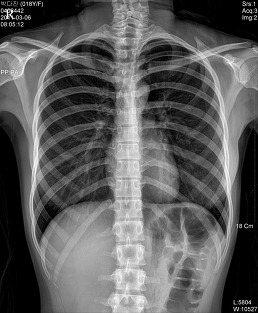

* CHEST PA (흉부 촬영)

♣검사목적

폐렴을 구분하거나 폐병소의 위치를 결정할 수 있다.

Central Ray

T-6 높이의 정중면에 수직으로 입사

Fillim Size

14 " X 14 ", 14 " X 17 "

Position

환자는 가능한 Erect Position을 취한다.

턱을 격자 장치 위에 올려놓고 두부의 정중면이 수직으로 놓이게 한 다음 견갑골이 흉부 외측으로 회전되도록 손바닥을 위쪽으로 향하게 한 상태로 양손을 둔부 위에 올려 놓는다.

Check Point

양측 쇄골의 휴골단은(sternal end)은 척추로부터 같은 거리에 놓여야 한다.

3~5cm의 폐첨부(apex)가 쇄골위에 보여야 한다.

posterior rib이 diaphram위에 보여야 한다.

척추로 부터 늑골의 외측연까지 거리는 양측 모두 같아야 한다.

심장 음영의 일부가 척추의 오른쪽에 나타나야 한다

심장과 diaphram의 윤곽은 뚜렷해야 한다

흉추와 양측 rib의 희미한 음영(faint shadow)이 심장 음영을 통해 보여야   한다.